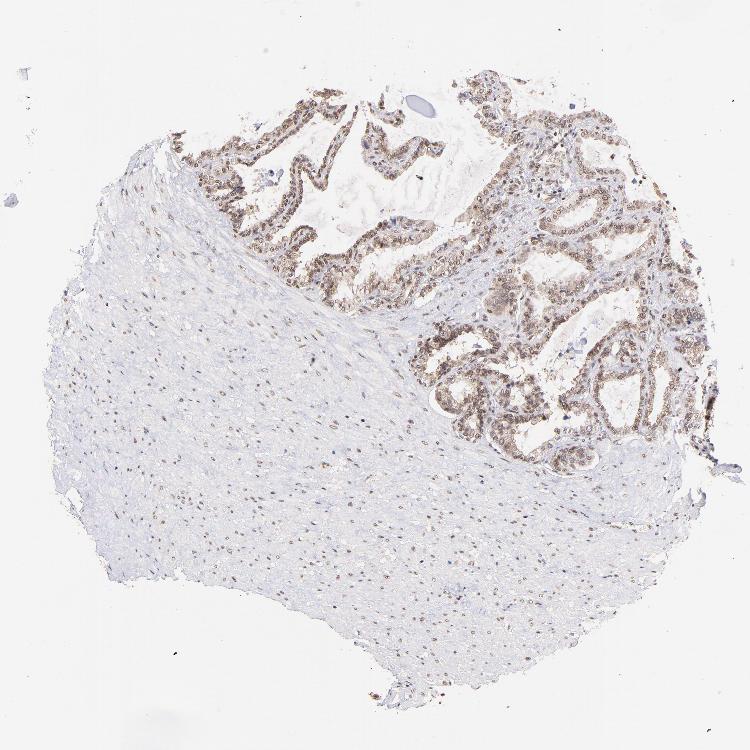

Antibody HPA003113

Glandular cells Medium